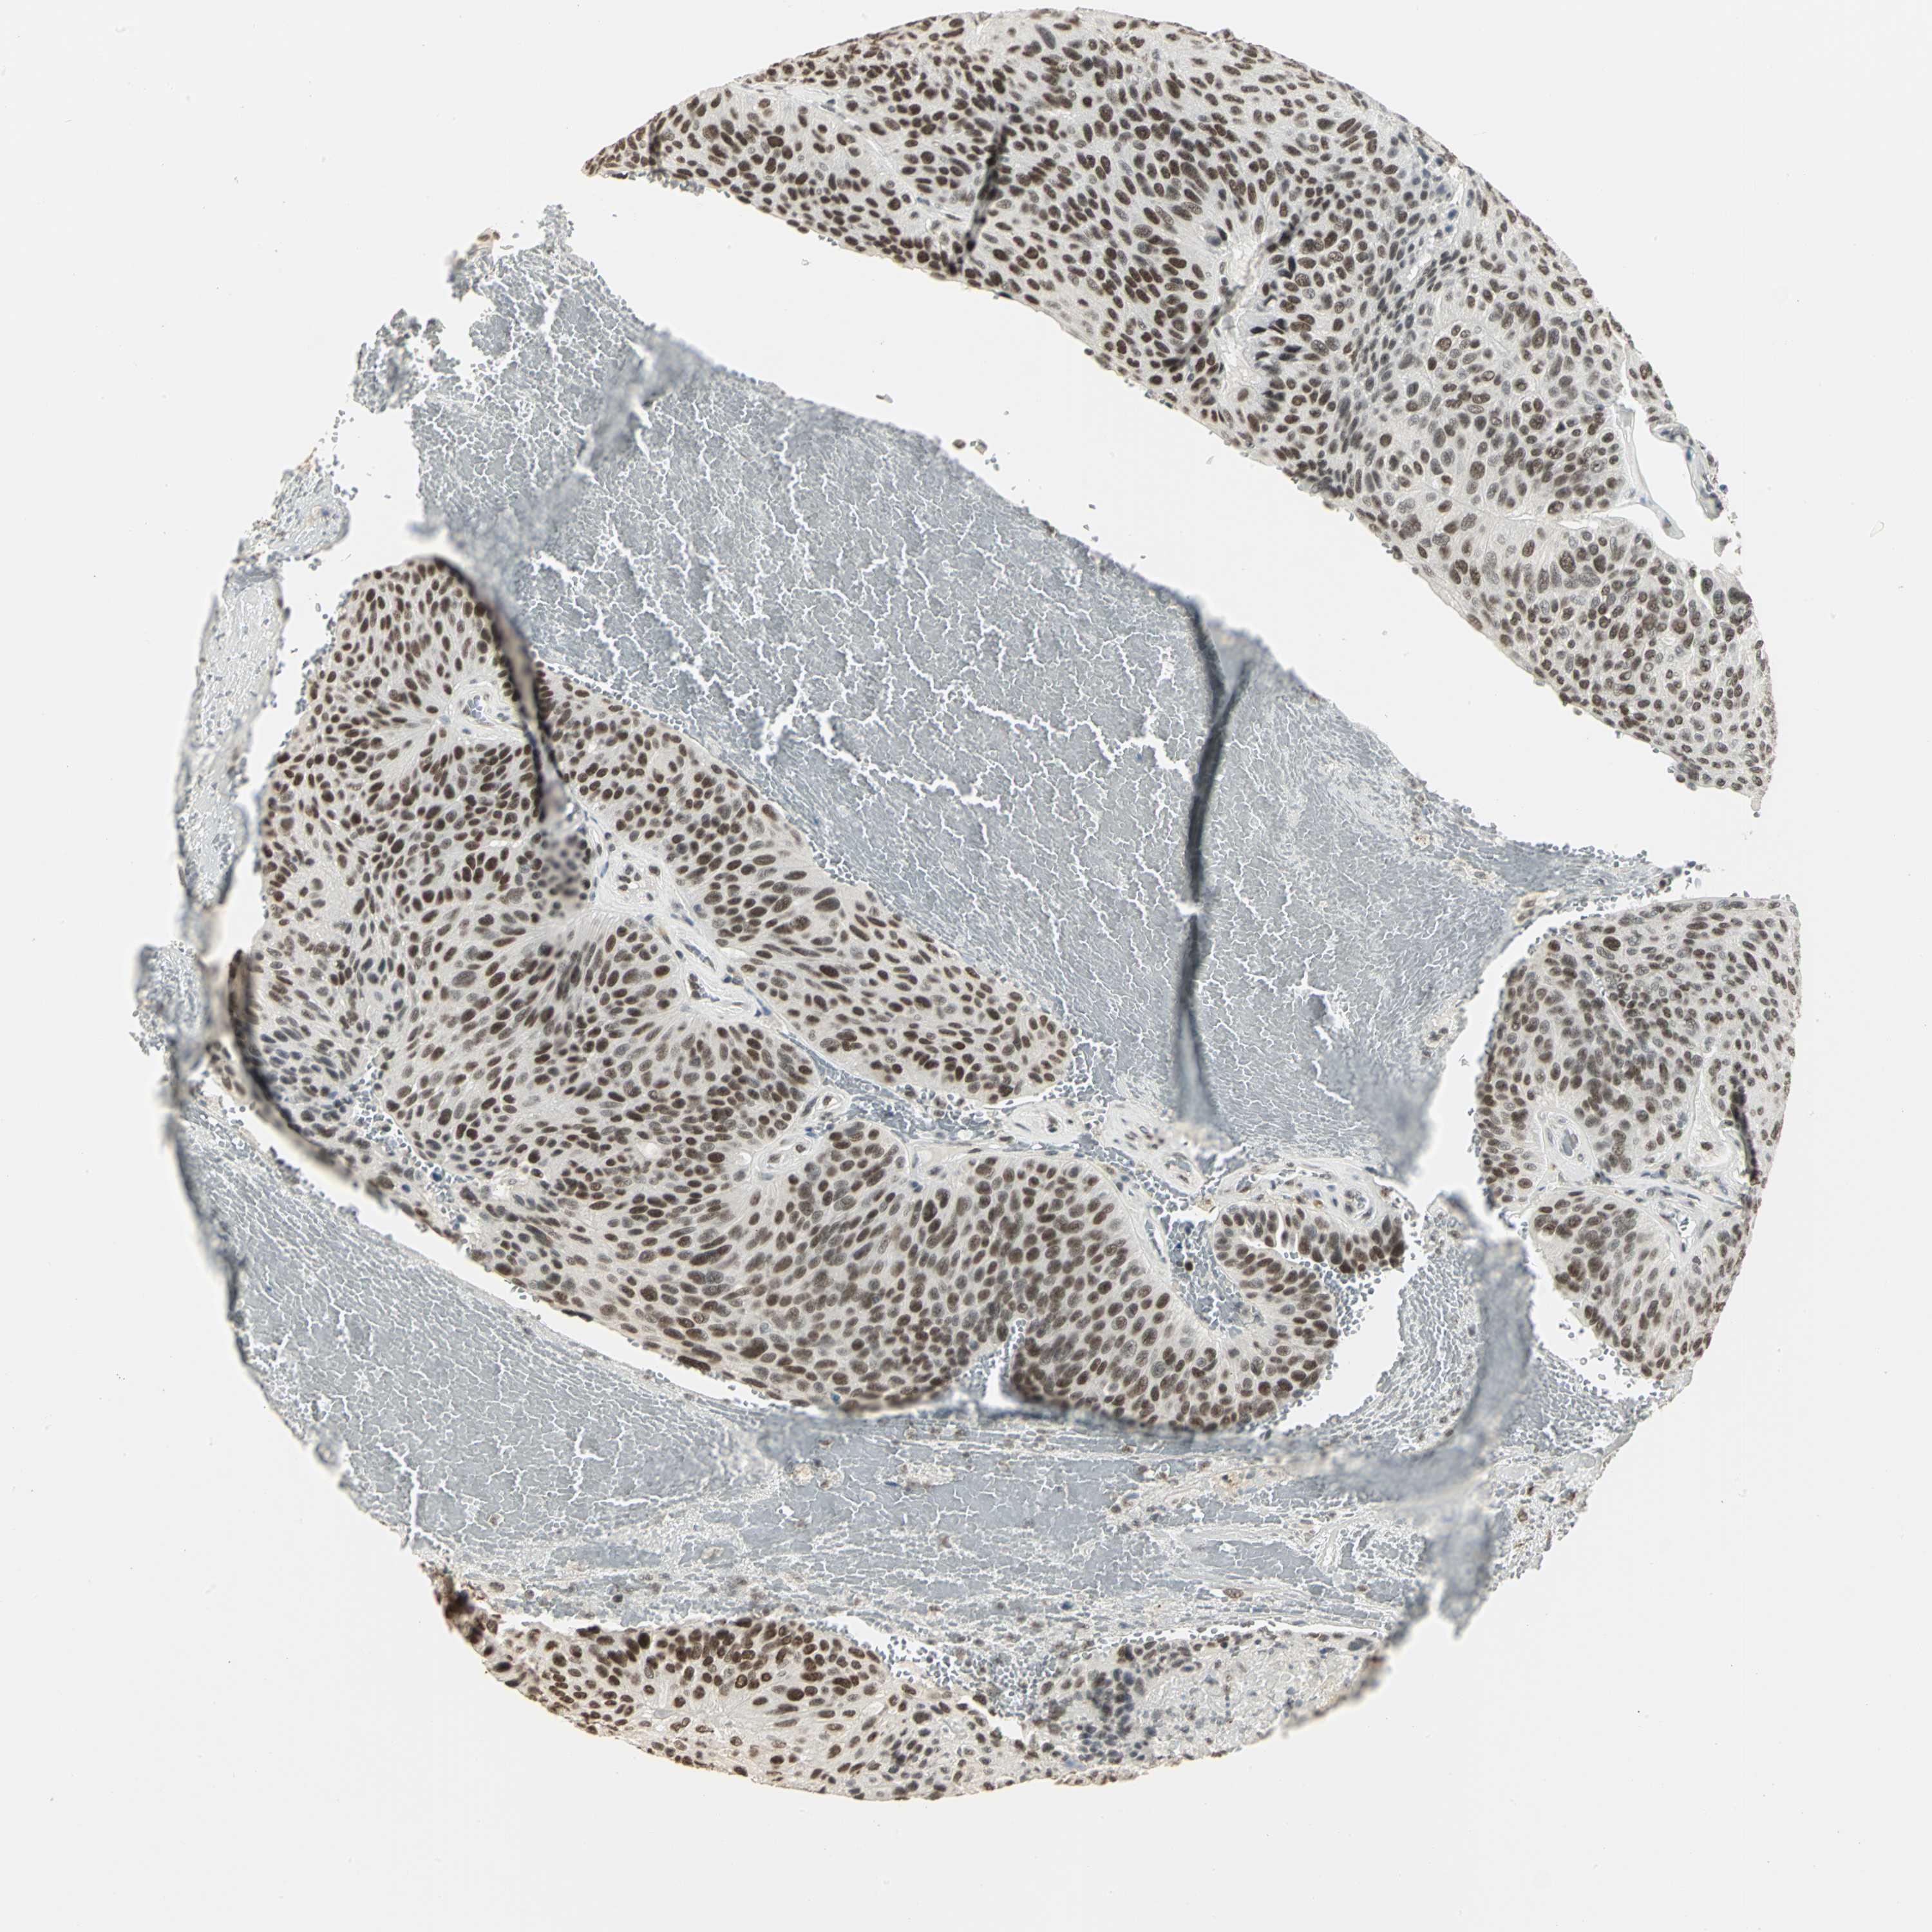

UROTHELIAL CANCER - Protein expressioni

A mouse-over function shows sample information and annotation data. Click on an image to view it in a full screen mode. Samples can be filtered based on level of antibody staining by selecting one or several of the following categories: high, medium, low and not detected. The assay and annotation is described here.

Note that samples used for immunohistochemistry by the Human Protein Atlas do not correspond to samples in the TCGA dataset.

Antibody stainingi

Antibody staining in the annotated cell types in the current human tissue is reported as not detected, low, medium, or high, based on conventional immunohistochemistry profiling in selected tissues. This score is based on the combination of the staining intensity and fraction of stained cells.

Each image is clickable and will lead to virtual microscopy that enables deeper exploration of all samples and also displays staining intensity scores, fraction scores and subcellular localization as well as patient and tissue information for each sample.

Antibody HPA004902

Antibody CAB001973

Staining

High

Medium

Low

Not detected

Intensity

Strong

Moderate

Weak

Negative

Quantity

>75%

75%-25%

<25%

None

Location

Nuclear

Cytoplasmic/membranous

Cytoplasmic/membranous,nuclear

Urothelial carcinoma, High grade

Urothelial carcinoma, Low grade

Adenocarcinoma, NOS